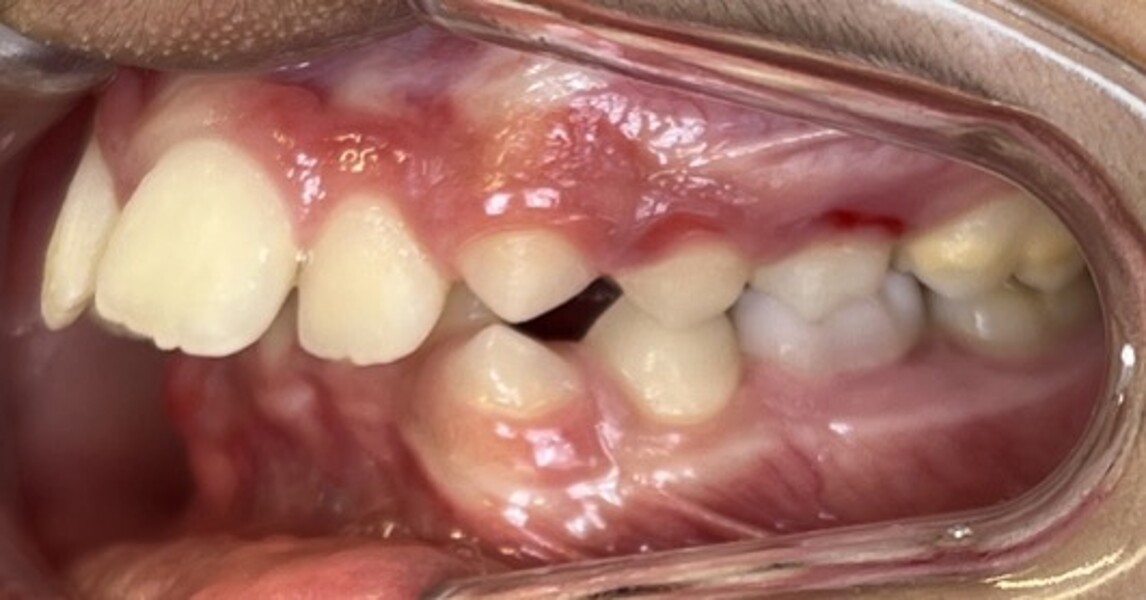

Figs. 2a–e: Pretreatment intra-oral photographs.

Clinical and radiographic evaluation revealed (Figs. 1–3):

a bilateral full-cusp Class II molar relationship;

an increased overjet of 11.7 mm;

a traumatic overbite of 7.2 mm; and

a narrow, collapsed V-shaped maxillary arch with a 2.0 mm midline deviation to the right.

Cephalometric analysis confirmed a Class II skeletal pattern primarily caused by mandibular retrusion (ANB = 5°; SNB = 69°) and showed reduced mandibular length (94 mm versus a norm of approximately 110 mm; Fig. 4; Table 1). The vertical pattern was normo-divergent (SN/GoGn = 34°). Dentoalveolar analysis showed severe maxillary incisor proclination, pronounced crowding in both arches and an accentuated curve of Spee. Soft tissue analysis showed lower lip entrapment associated with the increased overjet, contributing to an unfavourable facial profile.